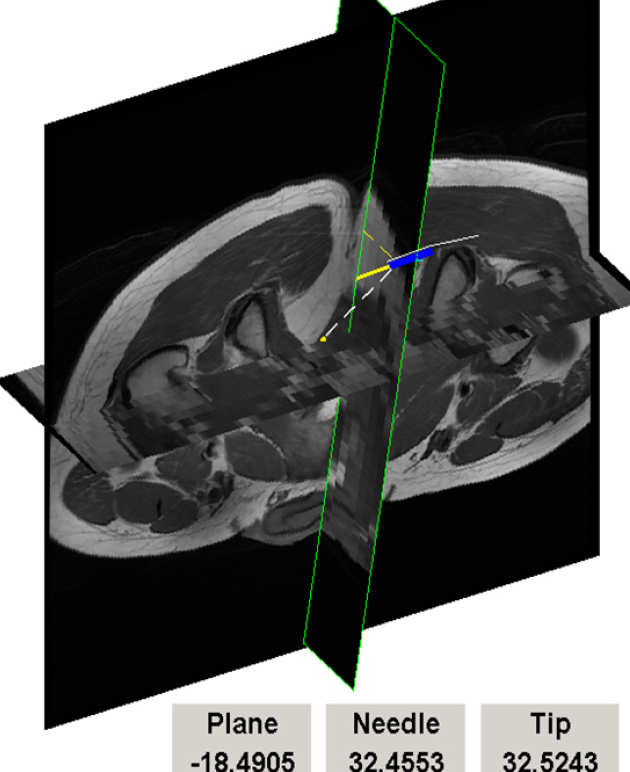

Design of the remote-centre manipulator (4 DOF) with the biopsy gun.

Owing to the direct tracking of the probe using MR sequences, there are no special registration nor calibration requirements at the start of the procedure.

Schematic layout during MRI guided biopsy procedure.

Manipulator configuration was designed to match the natural movements of the probe during the procedure.

Biopsy probe is inserted after the probe is aligned.

The patient remains in the scanner throughout the procedure.

Prototype in use in hospital MRI during trials with a realistic pelvic phantom. (right)

Interventional MR image feedback. Oblique sections through 3D image volume are automatically updated using probe position tracking and updated in real time. Synthetic image of the probe and guidance information are superimposed on MR image data. (below).